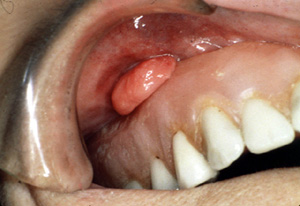

Este épulis fisurado se encuentra en una localización no habitual, en la almohadilla retromolar.

Este ejemplo extraño parece estar originando  porque la dentadura postiza irritaba la mucosa vestibular.